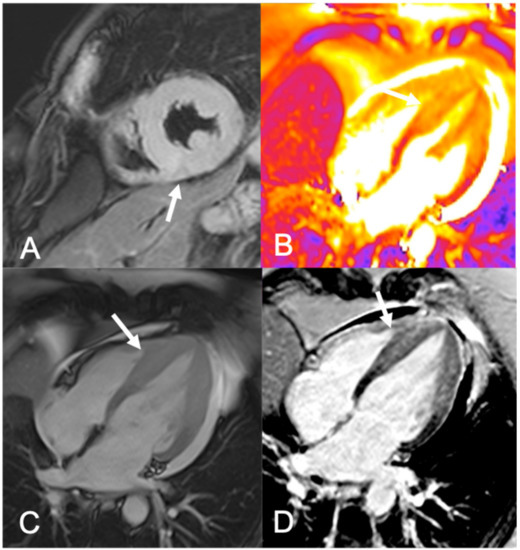

- Amano, Y.; Tachi, M.; Tani, H.; Mizuno, K.; Kobayashi, Y.; Kumita, S. T2-Weighted Cardiac Magnetic Resonance Imaging of Edema in Myocardial Diseases. Sci. World J. 2012, 2012, 1–7. [Google Scholar] [CrossRef]

- Anand, S.; Janardhanan, R. Role of cardiac MRI in nonischemic cardiomyopathies. Indian Heart J. 2016, 68, 405–409. [Google Scholar] [CrossRef] [PubMed]

- Buffa, V.; Di Renzi, P. CMR in the diagnosis of ischemic heart disease. Radiol. Med. 2020, 125, 1114–1123. [Google Scholar] [CrossRef] [PubMed]

- Hunold, P.; Schlosser, T.; Vogt, F.M.; Eggebrecht, H.; Schmermund, A.; Bruder, O.; Schüler, W.O.; Barkhausen, J. Myocardial late enhancement in contrast-enhanced cardiac MRI: Distinction between infarction scar and non-infarction-related disease. Am. J. Roentgenol. 2005, 184, 1420–1426. [Google Scholar] [CrossRef]

- Lee, E.; Ibrahim, E.S.H.; Parwani, P.; Bhave, N.; Stojanovska, J. Practical guide to evaluating myocardial disease by cardiac MRI. Am. J. Roentgenol. 2020, 214, 546–556. [Google Scholar] [CrossRef]

- Schiau, C.; Schiau, Ș.; Dudea, S.M.; Manole, S. Cardiovascular magnetic resonance: Contribution to the exploration of cardiomyopathies. Med. Pharm. Rep. 2019, 92, 326–336. [Google Scholar] [CrossRef]

- Baessato, F.; Guglielmo, M.; Muscogiuri, G.; Baggiano, A.; Fusini, L.; Scafuri, S.; Babbaro, M.; Mollace, R.; Collevecchio, A.; Guaricci, A.I.; et al. Stress CMR in Known or Suspected CAD: Diagnostic and Prognostic Role. Biomed. Res. Int. 2021, 2021. [Google Scholar] [CrossRef]